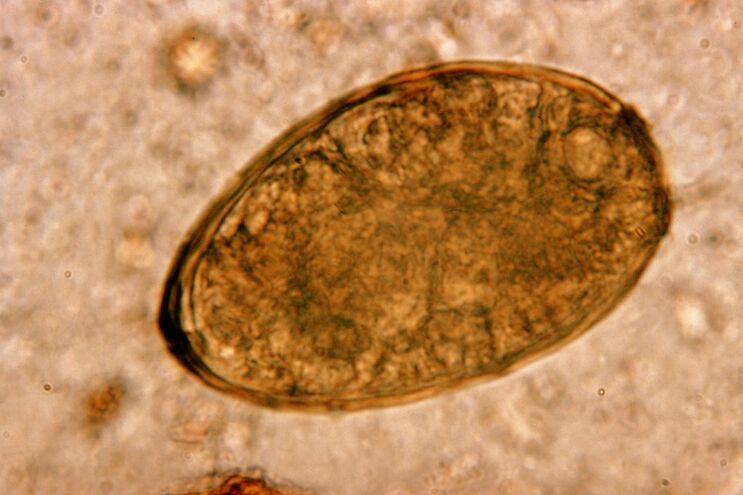

Roundworms, roundworms, live and reproduce in the intestines.Infection with them occurs through eggs that enter the body with food or from the hands and objects used by an infected person.Soil, fruits, vegetables, poorly cooked meat and fish - all this can introduce helminth eggs into the human body.

Worth knowing!Roundworms provoke a dry cough.Migrating through the circulatory system, their larvae enter the respiratory organs - bronchi, trachea, lungs - irritating the receptors and causing this symptom.The larval migration period throughout the body is one to two weeks.

Roundworms are very widespread, so coughing against the background of ascariasis is a typical phenomenon.Infection with roundworms occurs through the traditional routes for helminthiasis.These include contact with soil, eating unwashed fruits and vegetables, and dirty hands.

Ascaris larvae cause the problem by mechanically affecting the tissues of the respiratory system.This occurs during the migration phase of the parasite.The mechanism and sequence of the impact of roundworms on the human respiratory system is as follows.

After entering the gastrointestinal tract, roundworm eggs, under the influence of enzymes and their digestive juice, shed their shell, turning into larvae.The latter are equipped with the ability to penetrate through the intestinal wall into the bloodstream.After which they are carried by the blood throughout the body - reaching the liver, heart, lungs and respiratory tract.

In the mucous membrane of the trachea there are cilia, which transport the larva upwards with their reflex movements.In this case, the receptors are irritated and a cough appears, throwing helminths into the mouth, from where they are either spit out or swallowed, returning to the intestine.